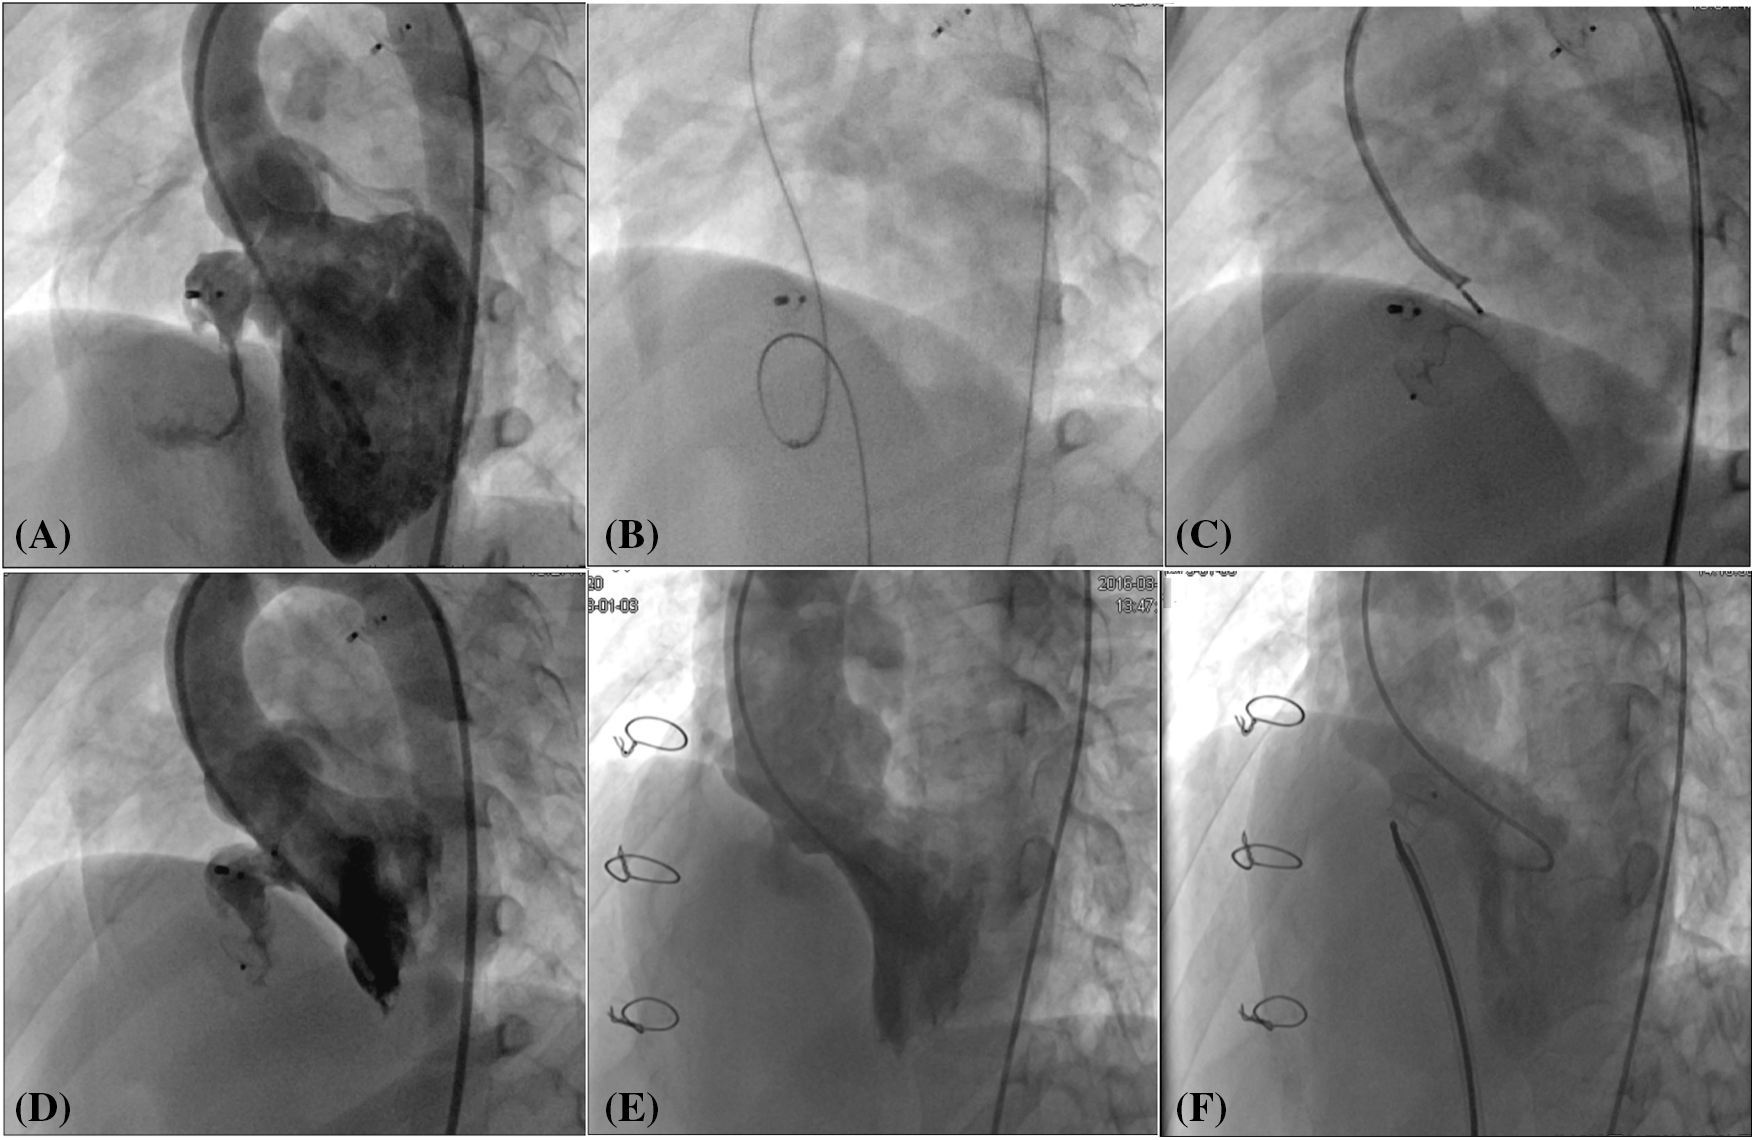

In this study, the TCC procedures were conducted by two skilled doctors with over 10 years of experience in CHD interventional treatment. We used the Amplatzer Septal Occluder (ASO, Abbott Medical, MN, USA), the Second-generation Amplatzer Ductus Occluder (ADOII, Abbott Medical, MN, USA), and a domestically manufactured atrial/ventricular septal occluder (Shanghai Shape Memory Alloy Co., Ltd., Shanghai, China). The choice of occluder was informed by transthoracic echocardiography (TTE), and left ventricular angiography, with the occluder’s positioning confirmed through fluoroscopy and TTE. TCC procedures were performed under local or general anesthesia, guided by both fluoroscopy and TTE. Access was obtained via puncture of the right femoral vein and/or artery, with a vascular sheath placed in the inguinal region. Patients received routine intravenous heparin administration at a dosage of 80–100 IU/kg. Standard right heart catheterization was conducted on all patients, followed by the TCC procedure as detailed in previous literature [5]. An appropriately selected occluder, attached to its delivery cable, was introduced through the femoral venous route using a delivery sheath and was precisely deployed at the designated site. Simplified illustrations of the TCC procedures for IAS (Fig. 1) and IVS (Fig. 2) are provided to offer visual clarity on the techniques employed.

Figure 2: Transcatheter closure of residual shunt following ventricular septal defect occlusion and surgical repair. (A) Angiography of the left ventricle revealed a protracted residual shunt at the periphery of the previously placed occluder. (B) An arteriovenous circuit was skillfully established. (C) A second-generation Amplatzer Duct Occluder was expertly implanted via the transfemoral artery route. (D) Subsequent angiography of the left ventricle post-occlusion confirmed the complete disappearance of the residual shunt. (E) In a patient with a residual shunt post-surgical repair of the ventricular septal defect, left ventricular angiography was performed to assess the situation. (F) Following the occlusion, a repeat angiography of the left ventricle demonstrated the residual shunt had vanished

As is shown in Table 2, 30 patients (11 males) had IVS: 2 patients following transcatheter VSD closure and 28 patients following surgical repair. The mean pulmonary arterial pressure, as determined by right heart catheterization, was 26.05 ± 10.13 mmHg with a QP/QS of 1.70 ± 0.35. The IVS diameter, assessed via left ventricular angiography, was on average 4.35 ± 1.70 mm, and the subaortic rim measured 4.16 ± 0.64 mm. TCC of IVS was successfully performed in 28 patients, while in two cases post-ventricular septal defect repair failed due to anatomical challenges involving the shape and aortic angulation. The average procedure time was 45.20 ± 20.30 min, and the fluoroscopy time was 11.50 ± 4.60 min. In the IVS cohort, three distinct device types were used: small-waist double-disk VSD occluders were employed in 14 cases, Symmetric double-disk VSD occluders in 5 cases, and ADO II devices in 10 cases.

The ADO II occluder is a soft, flexible, and self-expanding nitinol mesh device designed for minimally invasive implantation from either the arterial or venous side. This device features two retention discs on either side of the defect, connected by a central waist. The distinct advantage of the ADO II is its low profile requirement, necessitating only four or five French sheaths for deployment, which simplifies the procedure. After a thorough evaluation of our single-centre experience, we can confidently affirm that the ADO II is both safe and highly effective for TCC of residual shunts following CHD correction. It is particularly well-suited for elongated residual ducts and small residual VSDs [14]. In scenarios where residual ducts and VSDs are elongated and angulated, making it challenging to establish a circuit from the venous side, we opt for an arterial approach. Utilizing a right coronary artery catheter, we can delicately manipulate the guide wire, either withdrawing or advancing it as needed to traverse the residual shunt into the pulmonary artery or superior vena cava. The wire is subsequently snared to establish an arteriovenous circuit. Leveraging the unique structure of the ADO II, we can release the device through either arterial or venous access, providing flexibility in our interventional strategy. In the context of this study, the ADO II was deployed in 10 patients with residual VSDs, and in each case, it successfully achieved complete closure of residual shunts.